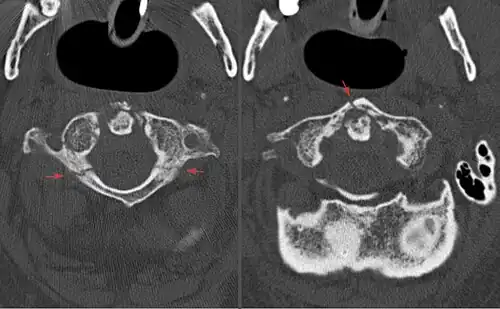

A Jefferson fracture is a bone fracture of the anterior and posterior arches of the C1 vertebra,[1] though it may also appear as a three- or two-part fracture. The fracture may result from an axial load on the back of the head or hyperextension of the neck (e.g. caused by diving), causing a posterior break, and may be accompanied by a break in other parts of the cervical spine.[1]

Diagnosis